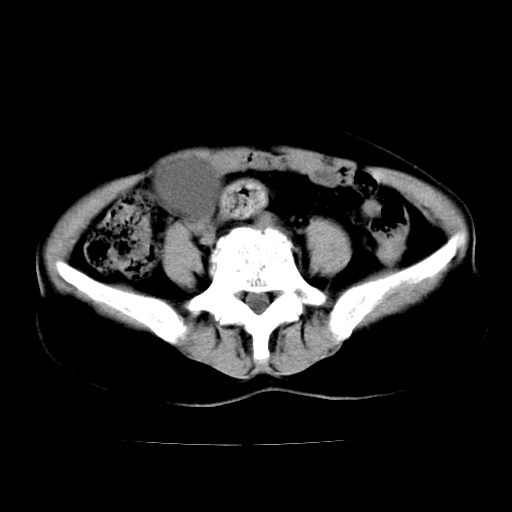

标题: CT24785:女,62岁,发现下腹部肿物半年。 [打印本页]

标题: CT24785:女,62岁,发现下腹部肿物半年。

女,62岁,发现下腹部肿物半年,下腹部不适。

考虑肠系膜间质肉瘤或脐尿管癌可能性大。

考虑回肠间质瘤,不排除卵巢癌可能。

该年龄性别首先考虑平滑肌肉瘤可能性大,其他待排除。

考虑子宫平滑肌肉瘤可能性大。